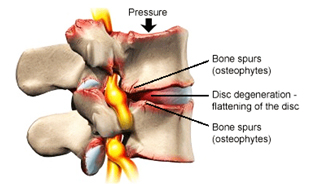

A spinal fusion procedure such as a TLIF may be recommended as a surgical treatment option for patients with a condition causing spinal instability in their lower back, such as degenerative disc disease, spondylolisthesis or spinal stenosis, which has not responded to conservative treatment measures (rest, physical therapy or medication). The symptoms of lumbar spinal instability may include pain, numbness and/or muscle weakness in the low back, hips and legs.